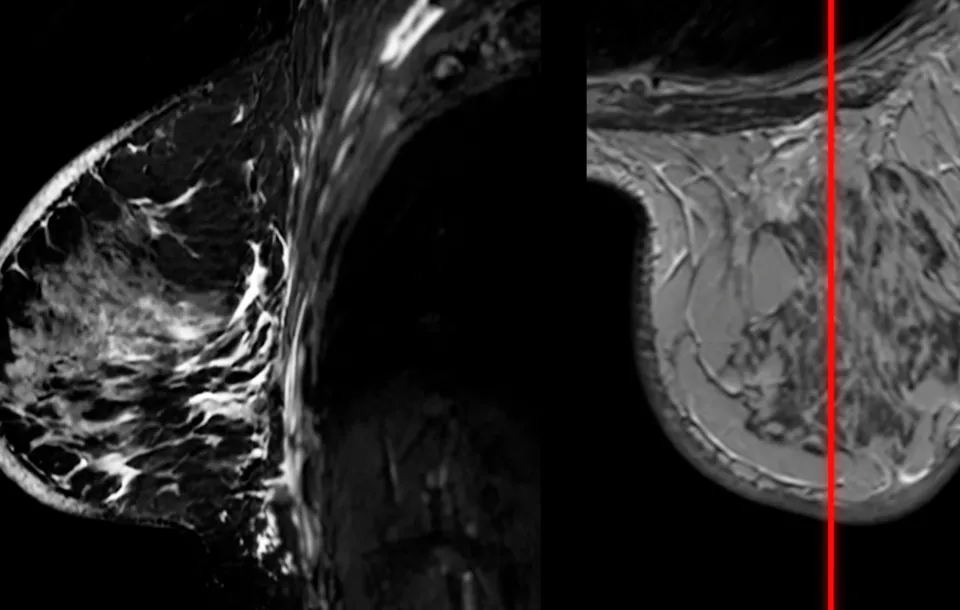

This webinar provides the most up-to-date insights on Breast MRI exams, exploring its advantages, limitations, and key differences from mammography and ultrasound in breast cancer detection. We’ll dive into the latest MRI breast protocols, including contrast-enhanced, breast implant, and abbreviated exams, discussing their clinical applications, benefits, and limitations.

Explain basics of MRI Breast imaging in comparison to Mammography and Ultrasound

Imaging identification and breast anatomy